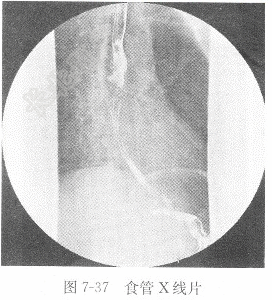

试题详情单项选择题男性,44岁,进行性咽下困难2周,食管造影图像见图7-37,X线诊断为( )。 A、食管静脉曲张B、食管癌C、反流性食管炎D、正常食管正确答案:关注下方微信公众号,搜题查看答案热门试题肝癌动脉血氧分压(PaO2)题见图6-12。心电图诊断步骤与报告内容胰腺癌男性,44岁,进行性咽下困难2周,食管造急性胆囊炎心脏扩大心室颤动检查脑出血题见图6-10。 肌酸激酶同工酶血清钠参考值气胸及液气胸脑脊液生化窦性心律心电图室性心动过速检查如何判断房性期前收缩代偿间歇是否完全?典型心肌缺血检查亚急性期血肿